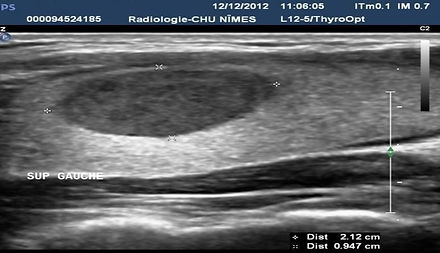

Cáncer papilar UE TIRADS 5

Cáncer papilar bien diferenciado con componente líquido dominante.

Nódulo sospechoso de malignidad en la citología.